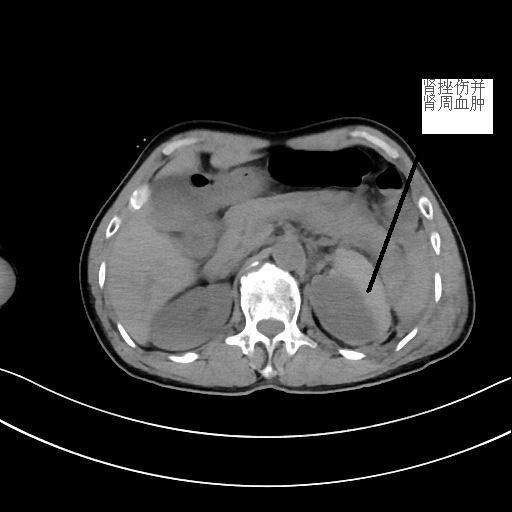

患者潘先生,因騎車摔倒入院搶救。入院時(shí),潘先生神志已模糊,無法對(duì)答,檢查檢驗(yàn)提示顱內(nèi)多發(fā)損傷,出現(xiàn)腦疝,病情危重,我院神經(jīng)外科團(tuán)隊(duì)緊急聯(lián)系福醫(yī)大附二院當(dāng)日值班專家來院開展開顱手術(shù)。經(jīng)及時(shí)搶救,患者病情穩(wěn)定,轉(zhuǎn)危為安。

<<<< 治療前后對(duì)比